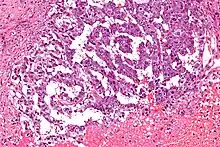

| Micrograph showing the yolk sac component of a mixed germ cell tumour. H&E stain. | |

EST can have a multitude of morphologic patterns including: reticular, endodermal sinus-like, microcystic, papillary, solid, glandular, alveolar, polyvesicular vitelline, enteric and hepatoid.

Schiller–Duval bodies on histology are pathognomonic and seen in the context of the endodermal sinus-like pattern. Rarely, it can be found in the vagina.[6][7]